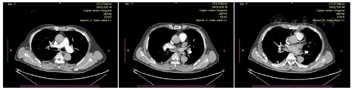

患者术后出现高热、炎症指标显著升高,伴心、肝、肾、造血功能不全,考虑"脓毒血症、多器官功能障碍综合征",CCU团队制定诊疗方案,同时在呼吸科、血液科、肾内科等多学科的协助下,对患者病情精准评估,给予抗凝、抗感染、血管活性物质维持血压、镇静、补液扩容、营养支持及高级生命支持等积极救治。患者意识逐步恢复,生命征平稳,多脏器功能障碍得到纠正,且通气氧合情况改善,于2022年4月16日拔除经口气管插管,2022年4月25日转入普通病房继续抗凝、抗感染等治疗。复查下肢静脉彩超提示右侧胫后静脉、腓静脉及小腿肌间静脉实体回声(血栓?);CT肺动脉造影提示肺动脉栓塞术后,右下肺动脉栓塞,较前好转。于2022年5月7日行"下腔静脉滤器取出术",根据凝血情况桥接华法林口服继续抗凝治疗。

患者术后第14天转入心血管内科普通病房治疗,因口服华法林监测INR未达标,改为口服利伐沙班抗凝,并在普通病房治疗后康复出院。患者出院后1个月门诊随访无复发。